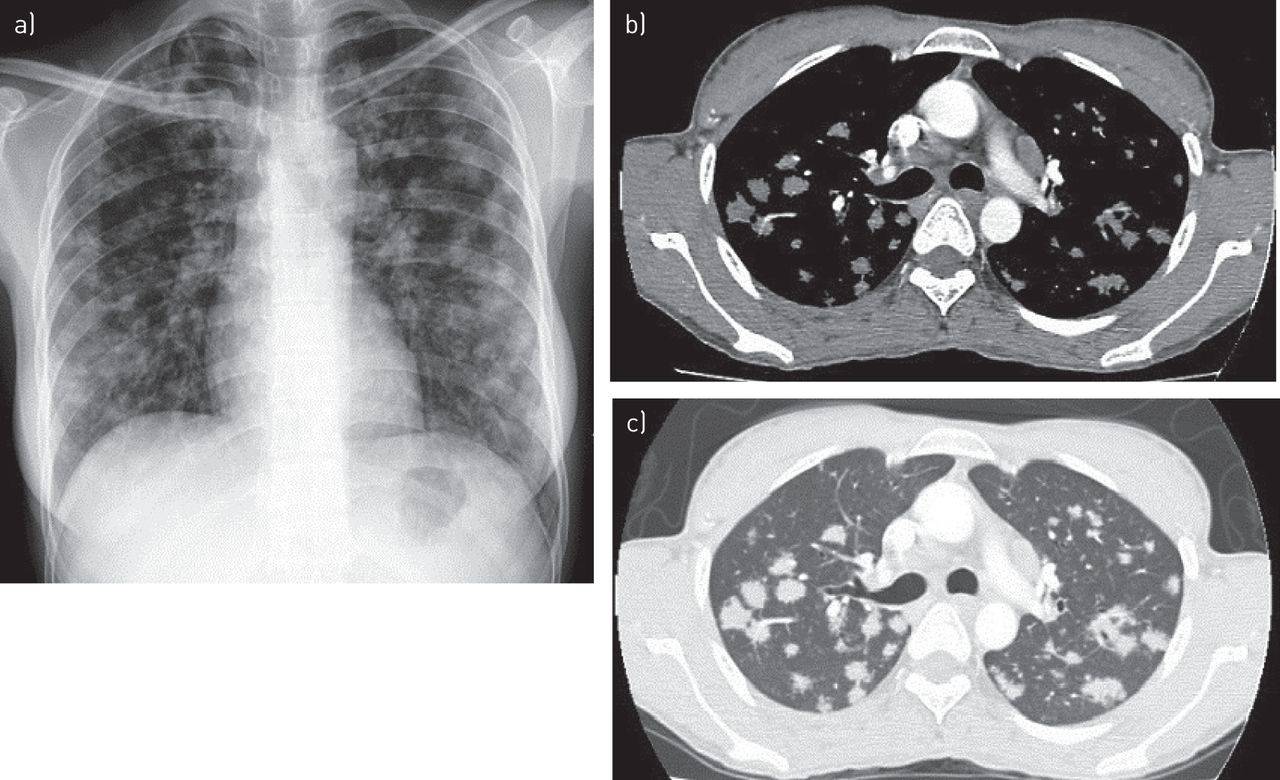

Диагностика туберкулеза возможна по результатам рентгенографического обследования, цианобактериальных мазков, кожной пробы. Прецизионная диагностика туберкулезных поражений легочной ткани (локализация, плотность инфильтратов) возможна только на компьютерной томографии.

Виды туберкулеза легких: КТ-картина

КТ легких не показывает конкретного возбудителя туберкулезной инфекции из класса микобактерий, однако показывает изменения в легких которые не видны на обычном рентгене или флюорографии из-за сравнительно низкой разрешающей способности последних, неполного обзора, эффекта наложения теней, который искажает результаты диагностики.

По специфической КТ-картине рентгенологи определяют следующие виды туберкулеза:

- Туберкулез внутригрудных лимфатических узлов (синдром инфильтрации корня легкого и синдром полициклически измененного корня легкого) — бактериальное поражение лимфатических узлов грудной клетки и средостения, поражение легких при этом отсутствует.

- Милиарный туберкулез (синдром милиарной диссеминации) — характеризуется наличием множественных просовидных бугорков в легких, расположенных сравнительно равномерно.

- Диссеминированный туберкулез легких —множественные очаги туберкулеза в обоих легких имеют разную величину и расположены диффузно.

- Очаговый туберкулез —характеризуется наличием одиночных или множественных очагов до 1 см в диаметре. Если очагов несколько, то расположены они в одном месте.

- Инфильтративный туберкулез легких —характеризуется наличием бронхо-пневмонического воспаления, формирования участка инфильтрации легочной ткани, более 1 см в диаметре.

- Кавернозный туберкулез легких —характеризуется формированием полости деструкции, распада легочной ткани в следствии запущенного инфекционного процесса, так называемой каверны круглой или овальной формы.

- Фиброзно-кавернозный туберкулез —наряду с кавернами в легких присутствуют признаки фиброза, который является агрессивной ответной реакцией организма на воспаление и деформирует матрикс легкого в легких формируются туберкулезные рубцы).

Первичный туберкулезный комплекс (ранняя стадия заболевания) характеризуется наличием очага или их группы в легких, увеличением лимфоузлов. На КТ с одной или, чаще всего с обеих сторон в долях легких визуализируются уплотнения – сравнительно более светлого цвета, чем вся легочная паренхима, имеют специфическую, отличную от легочного матрикса, сосудов и бронхов форму.

Ежегодная профилактическая флюорография — быстрое, доступное и, безусловно, полезное обследование. Но данный рентгенографический метод, изобретенный в первой половине XX века с наибольшей вероятностью покажет туберкулез «в общем» и на более поздних стадиях. Поэтому более предпочтительным методом диагностики туберкулеза сегодня считается скрининговая низкодозная КТ легких (МСКТ легких).

Преимущества КТ перед другими рентгенологическими методами обследования:

- Показывает изображение аксиальной плоскости, позволяет воссоздать детализированную аутентичную 3D-модель легких больного, что недоступно при флюорографии и рентгене;

- Позволяет достоверно оценить плотность, размер, форму инфильтратов; определить объем туберкулезного поражения легких;

- Расширяет возможности внутривенного контрастирования для оценки мягких тканей, грудных артерий, лимфоузлов;

- Есть возможность денситометрической обработки изображения.